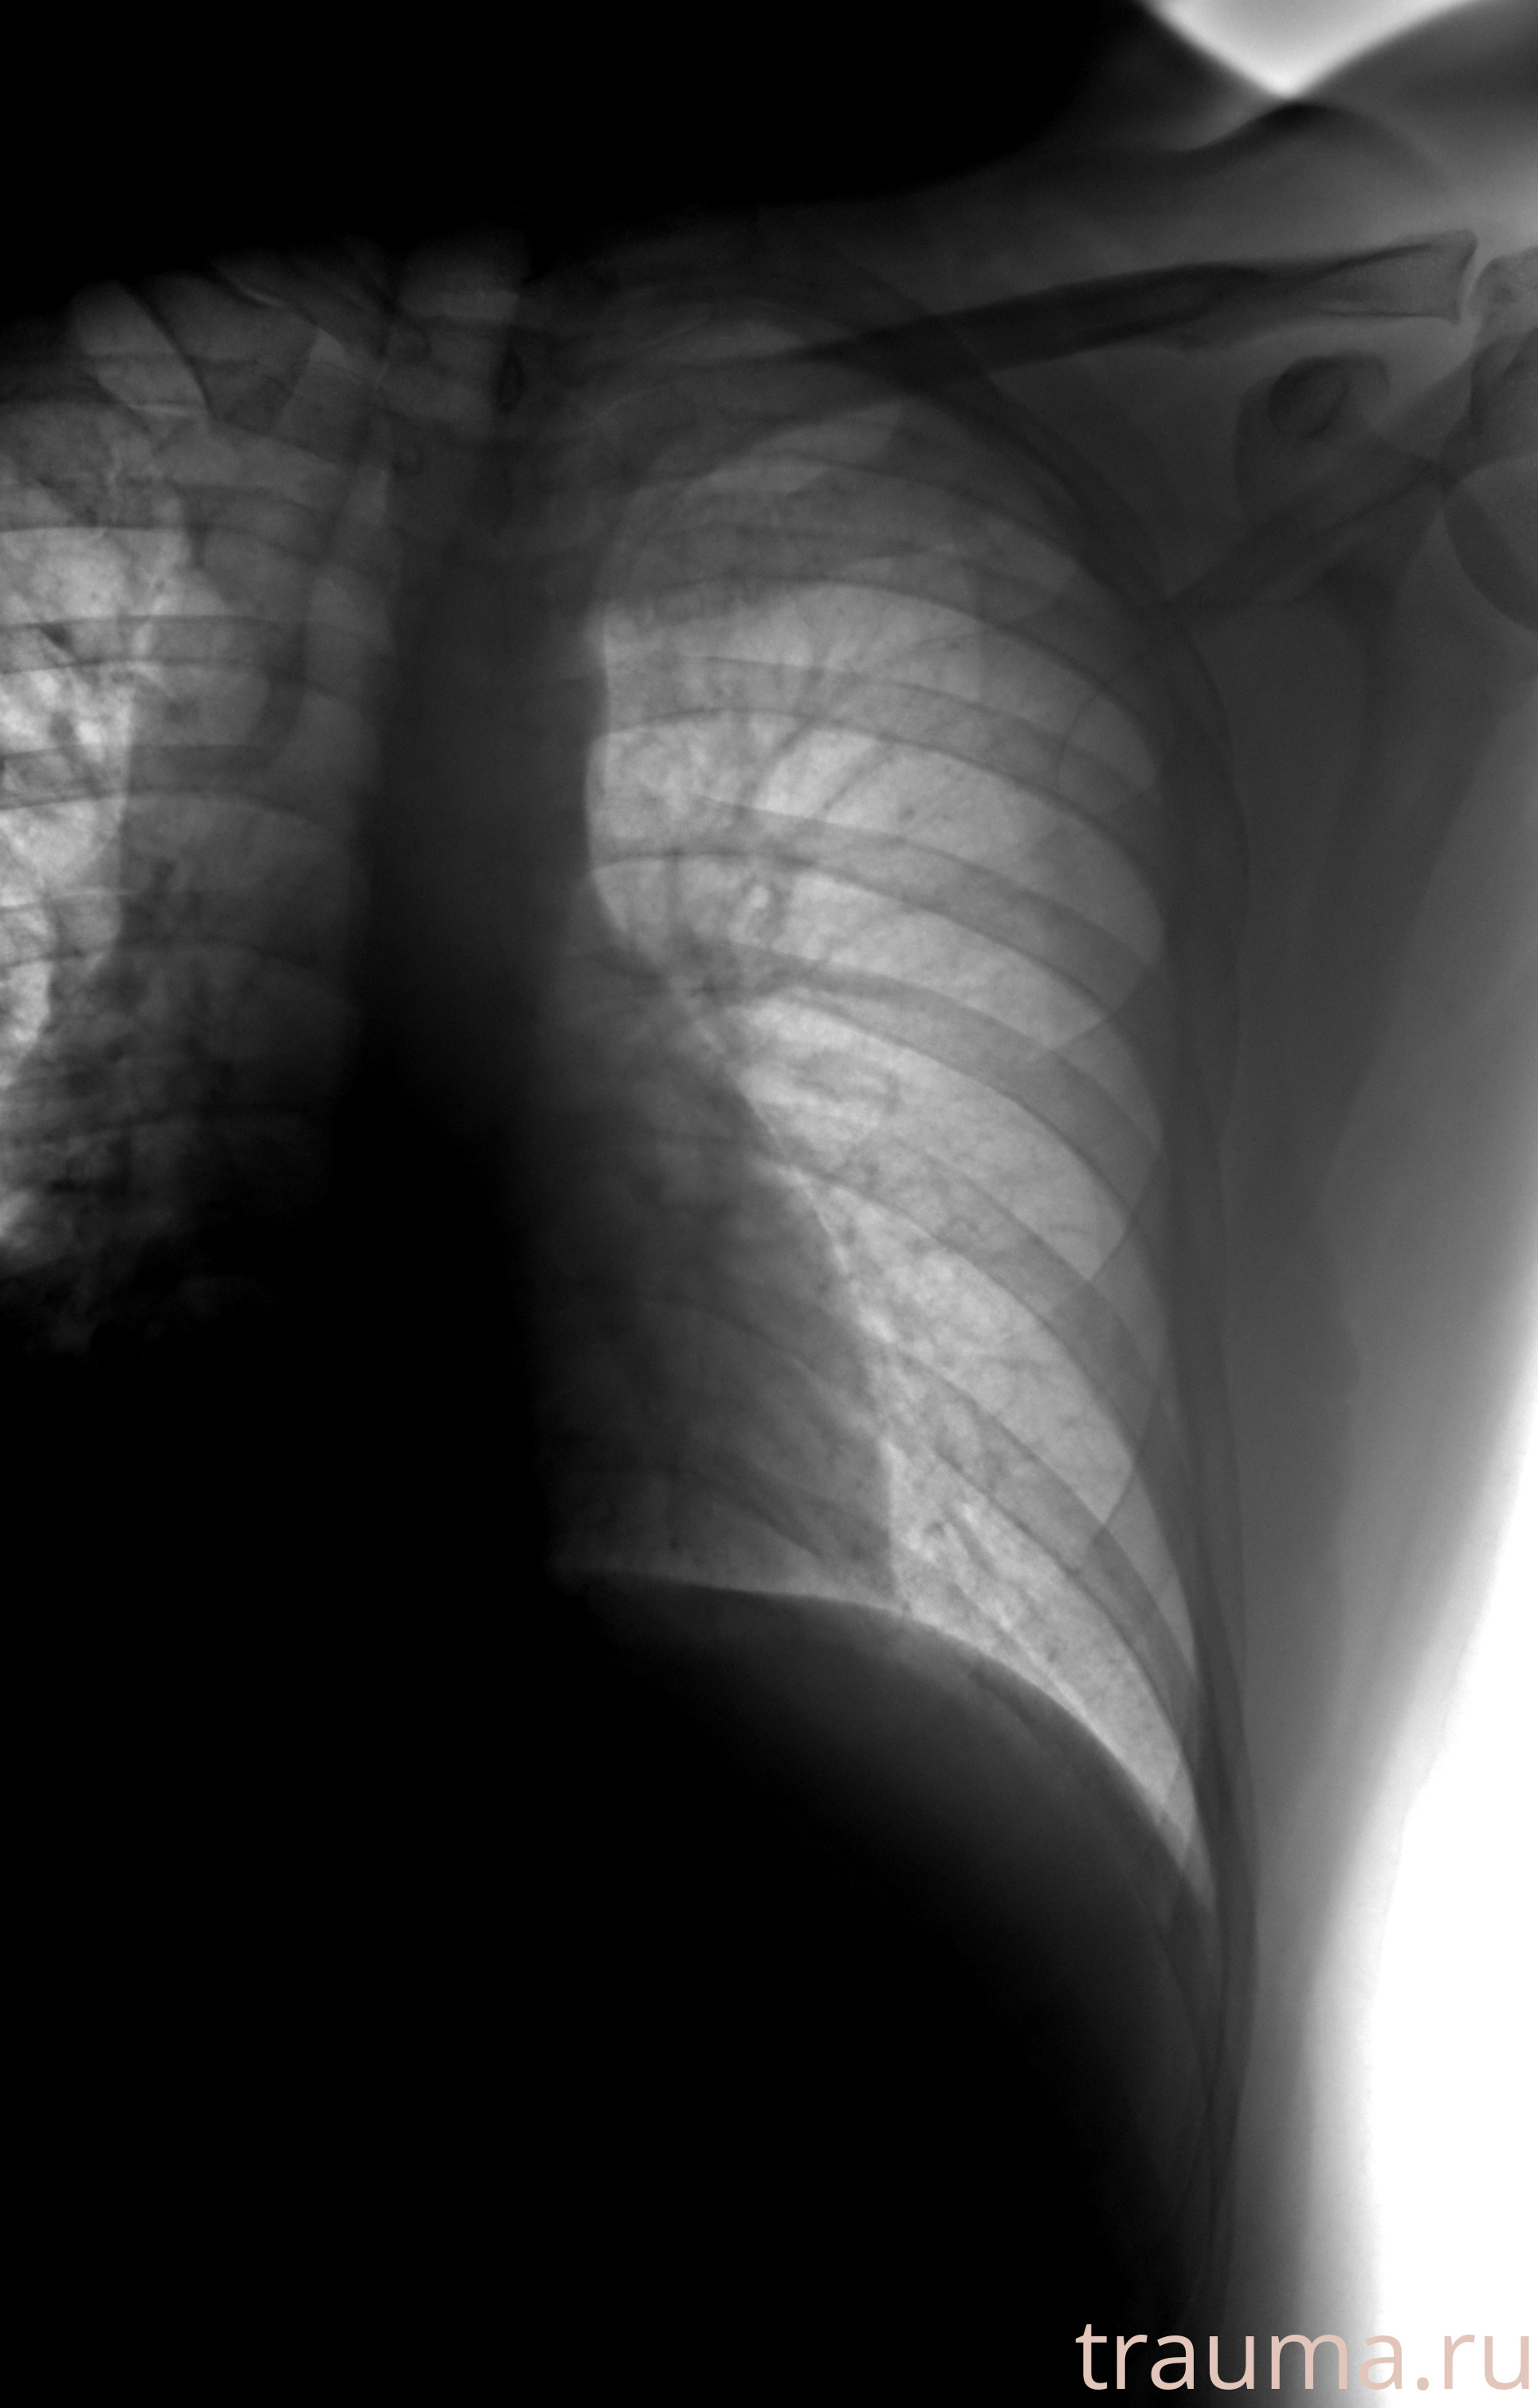

Рентгенограммы

Рентген на дому: по вашему адресу приезжает врач-рентгенолог, травматолог-ортопед с мобильным рентгеновским аппаратом, проводит диагностику травмы или заболевания, делает необходимые рентгенограммы, дает рекомендации по дальнейшему лечению. Получить качественные снимки в домашних условиях возможно благодаря уникальной методике, разработанной МосРентген Центром для института  Склифосовского